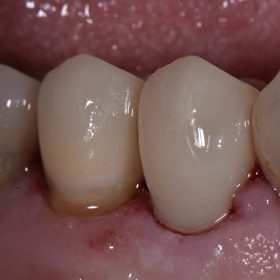

Mercury-Free Fillings | Wear Repair | Composite Resin Front Teeth

With modern bonding technology, we often don’t need to drill at all to reverse years of damage on teeth. This case is a prime example. This lady had years of […]